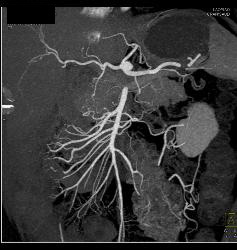

Fibromuscular Dysplasia (FMD) of Right Renal Artery the Mesenteric Vessels Were Normal